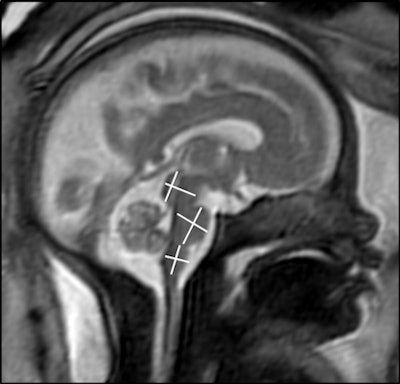

A team led by Dr. Sophia Stöcklein from the Ludwig Maximilian University of Munich in Germany found normal fetal brain development, including cortical folding and brain stem segmentation, in their study of fetuses whose expectant mothers had COVID-19.

The team found that brain development characteristics, such as opercularization of the Sylvian fissure, cortical folding, and transverse cerebellar diameter were age-appropriate in all fetuses. They also found that the diameter and craniocaudal extent of the pons, medulla oblongata, midbrain, and cerebellar vermis were all within age-appropriate limits.

"No calcifications, edema, or ventricular enlargement were detected. Seven fetuses showed mild asymmetry of the lateral ventricles with a maximum difference of 4 mm," they wrote.